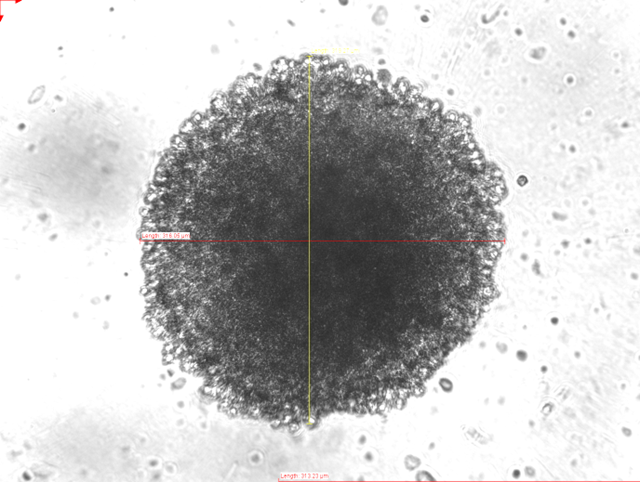

In addition to performing chemical syntheses of new molecules in the wet lab, our group also runs a cell culture lab. Here, we perform first investigations on the biological activity of our new metal complexes and bioconjugates. We carry out cytotoxicit and viability assays, study metabolism and cell death mechanisms, and investigate compound localization intra-cellularly by fluorescence microscopy. More recently, we have expanded the traditional "2D" cell culture (where cells are grown and studied as monolayers in flat-bottom plates) to 3D cell culture, where cancer cells grow in three dimensions, so-called "spheroids". In comparison to monolayer cell cultures, these multi-cellular tumour spheroids (MCTS) are able to accurately simulate many features of in vivo human solid tumours, such as their spatial architecture, physiological responses, secretion of soluble mediators to facilitate inter-cellular communicaton, gene expression patterns, and drug resistance mechanisms.

We study the anti-proliferative activity of synthesized compounds in 2D cell culture and solid 3D tumor spheroids, and we develop metal-based imaging dyes so as to detect intracellular localization of metal complexes and metabolic activity. More advanced biomedical experiments and techniques are carried out with our collaborators in the Medical Faculty at RUB, and elsewhere. In collaboration, we also use confocal microscopy and advanced techniques like lifetime imaging (FLIMS).